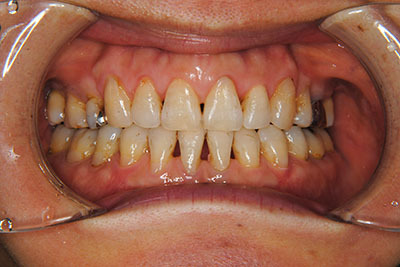

おとなの方でも矯正治療をあきらめないでください!

いくら歯が動き易くとも、本人がやる気でなければ効果は出ませんし、むし歯発生のリスクも高まります。おとなの方は顎の成長が終わっているため、治療の計画が立てやすいとも言えます。「もう大人だから…」とあきらめず、一度ご相談ください。